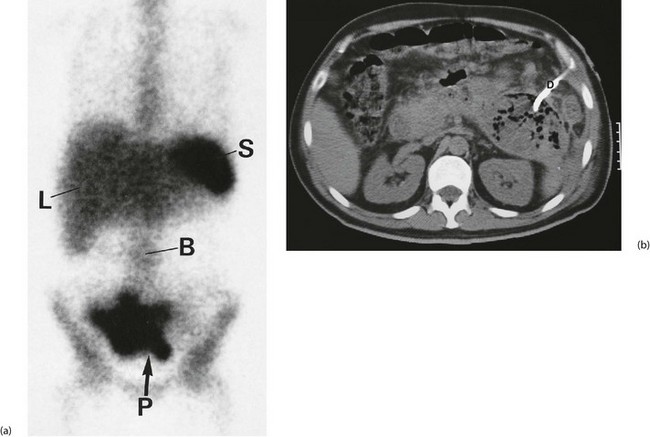

Investigation involves colonoscopy, usually once the bleeding has stopped. Occasionally an unsuspected carcinoma or polyp is discovered. In ulcerative colitis, the diagnosis is evident from the other symptoms and signs, and management depends on the success of medical treatment (see Ch. 28). Persisting large bowel haemorrhage which is less rapid but recurrent is usually due to angiodysplasias (see Ch. 29). Colonoscopy can be both diagnostic and therapeutic for bleeding angiodysplasia. If colonoscopy is negative, impossible or unsatisfactory, radioisotope scanning using the patient's own labelled red cells can be used; this has the advantage of identifying bleeding at rates as low as 0.05 ml/min. Highly selective arteriography is increasingly used in diagnosis of gastrointestinal haemorrhage but relies on much more rapid bleeding (greater than 0.5 ml/min) (see Fig. 19.12). At the time of arteriography, bleeding can be controlled with localised delivery of vasopressors or by coil embolisation.